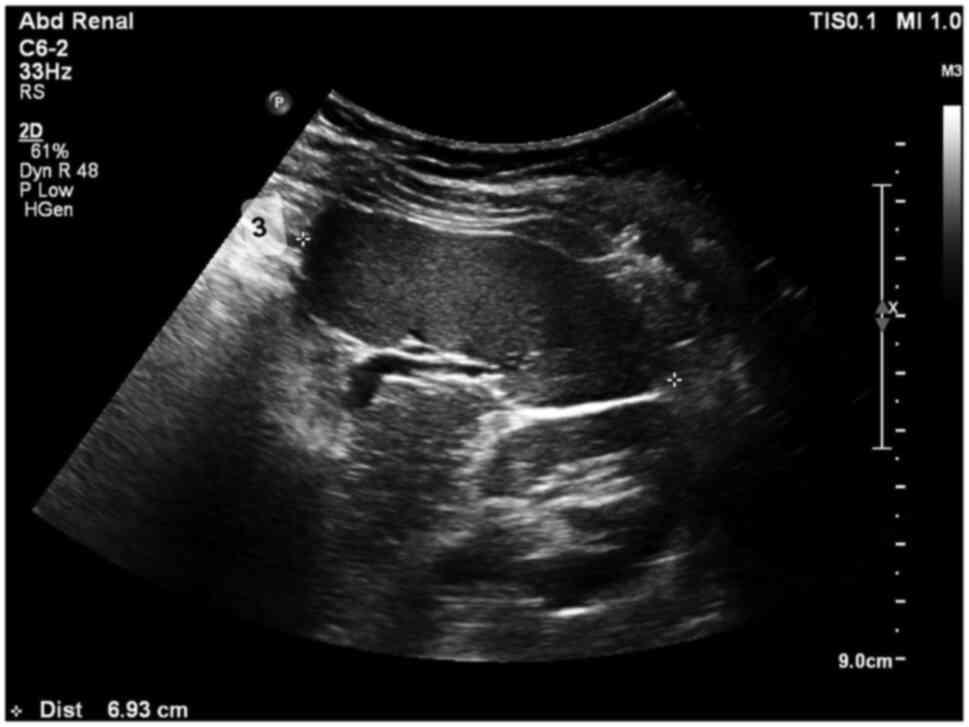

A longitudinal section (coronal oblique view) was obtained with the transducer aligned parallel to the intercostal spaces in the left upper quadrant, with the maximum diameter between superomedial and inferolateral points (length). The perpendicular diameter from the hilum to the lateral surface of the spleen (thickness) was measured in this section (Fig. 1). The transducer was then rotated 90˚ counterclockwise to image the spleen in the transverse section, and the anteroposterior diameter (width) was measured in this section (Fig. 2).

Spleen diameters at the level of the hilum in a longitudinal flank. In the scanned image, 1 refers to length and 2 to thickness.

Spleen diameter at the level of the hilum in transverse. In the scanned image, 3 refers to width.